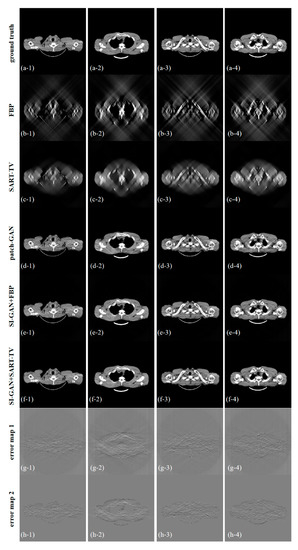

| avg. PSNR | avg. RMSE | avg. NMAD | avg. SSIM | |

|---|---|---|---|---|

| SART-TV | 15.117 | 0.0407 | 0.9306 | 0.6149 |

| patch-GAN | 27.460 | 0.0141 | 0.2033 | 0.9327 |

| SI-GAN + SART-TV | 29.820 | 0.0097 | 0.1467 | 0.9588 |